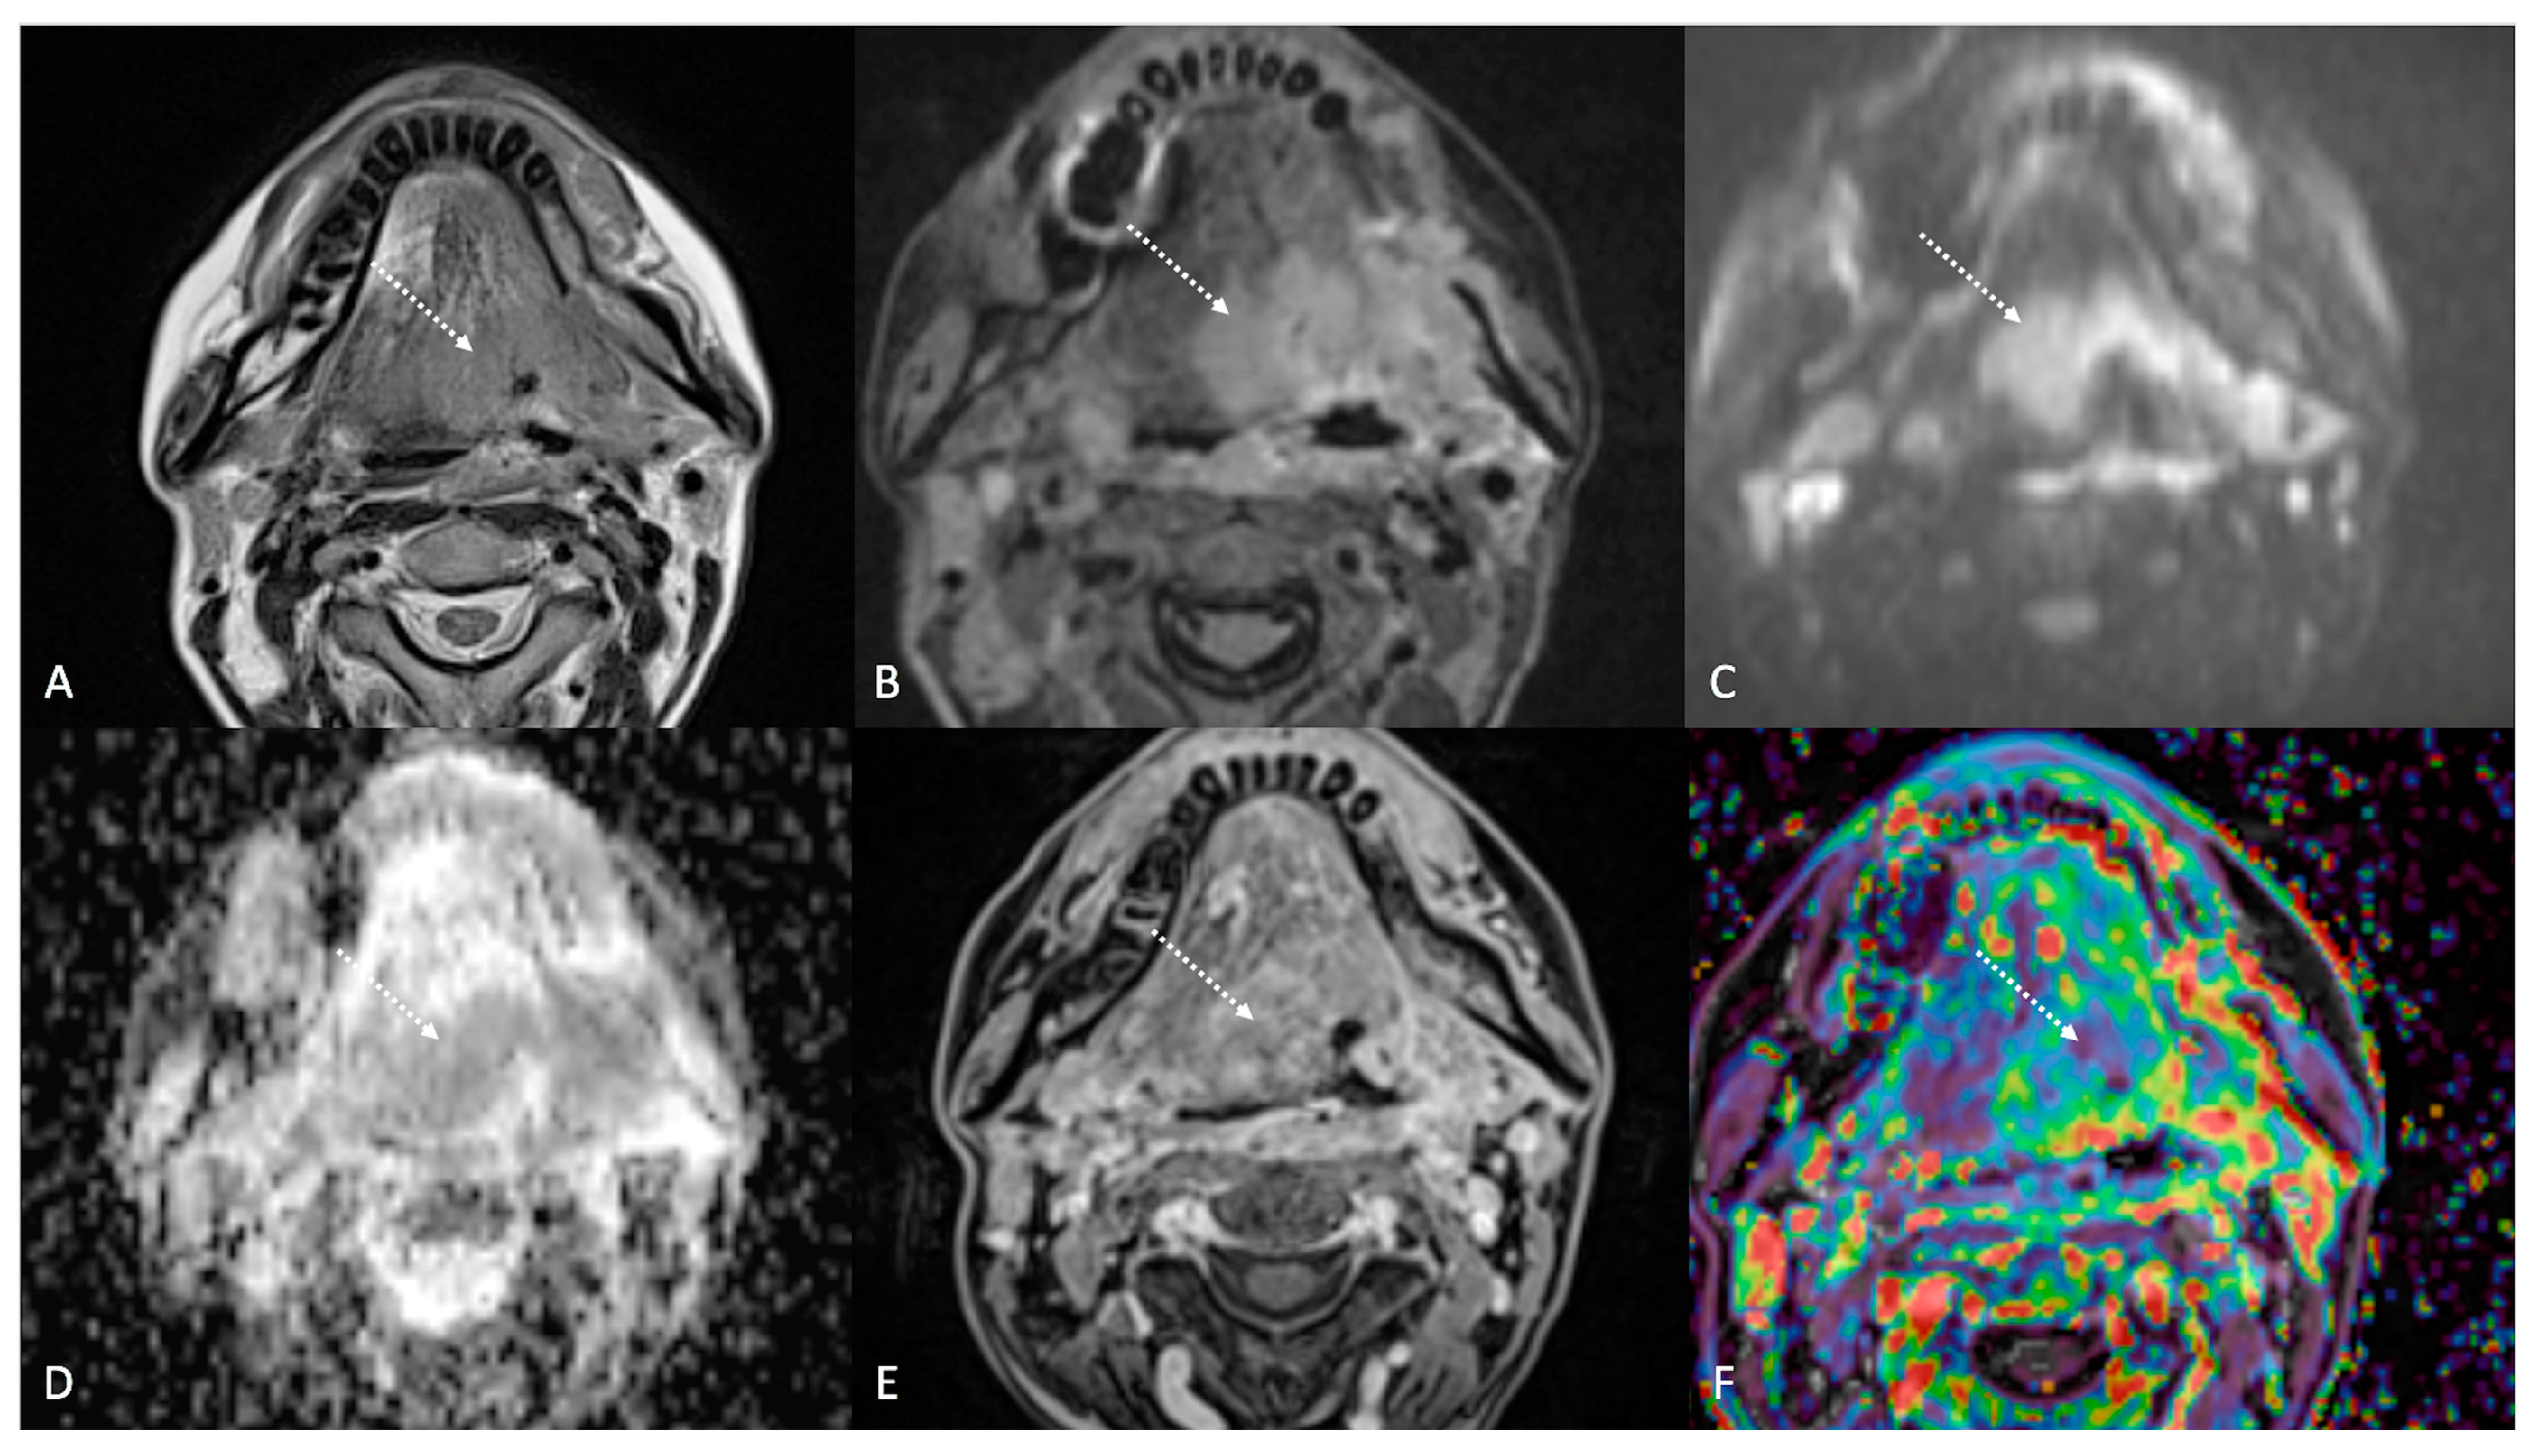

Figure 4.

Post-treatment magnetic resonance imaging (MRI) of a 36-year-old female patient affected by nasopharyngeal carcinoma with left lymph node metastasis (T3N3) and tumoral extension to bilateral Ronsemüller fossa, left nasal choana, and middle skull base, recently treated (3 months before) with chemoradiotherapy (CRT). Early post-treatment MRI demonstrated post-CRT inflammatory residual tissue (white striped arrows) in the left Ronsemüller fossa and ipsilateral nasal choana. Post-CRT inflammatory changes showed hyperintense signal on T2-weighted (A), T2-weighted fat-saturated (B), and diffusion-weighted b800 images (C); high apparent diffusion coefficient value (1.53 × 10−3 mm2/s) (D). After gadolinium contrast agent injection, post-CRT inflammatory residual tissue shows submucosal enhancement of 5 mm thickness (E), and very high K(trans) value (595.25 × 10−3 mm2/s) on dynamic contrast enhancement-perfusion weighted imaging (F). Ratio between K(trans) values of the primitive tumor and residual tissue after CRT, standardized with respect to K(trans) value of the ipsilateral trapezius (K(trans)post/pre/muscle), was 3.17. These findings suggested an increase in capillary permeability caused by CRT.